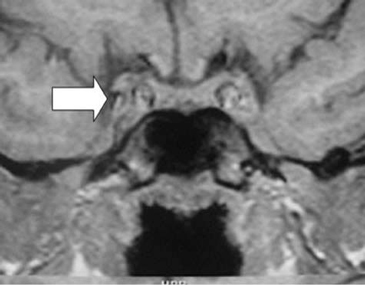

Posterior a la cirugía, se mantiene con tratamiento hormonal de reemplazo con normalización de los niveles de T4 (7,3 ug/dL) y cortisol (12,7 ug/dL). La medición de anticuerpos antihipofisiarios, antitiroideos y antiadrenales resultó negativa. Una nueva RNM al séptimo mes de la cirugía, mostró desaparición completa de la masa descrita. (Figura 3 y Figura 4). En estas imágenes se observa una glándula hipófisis de tamaño y morfología normales, con intensidad de señal homogénea. En los cortes sagitales se aprecia tenuemente la hiperintensidad de la señal neurohipofisiaria y no se reconocen lesiones satélites.